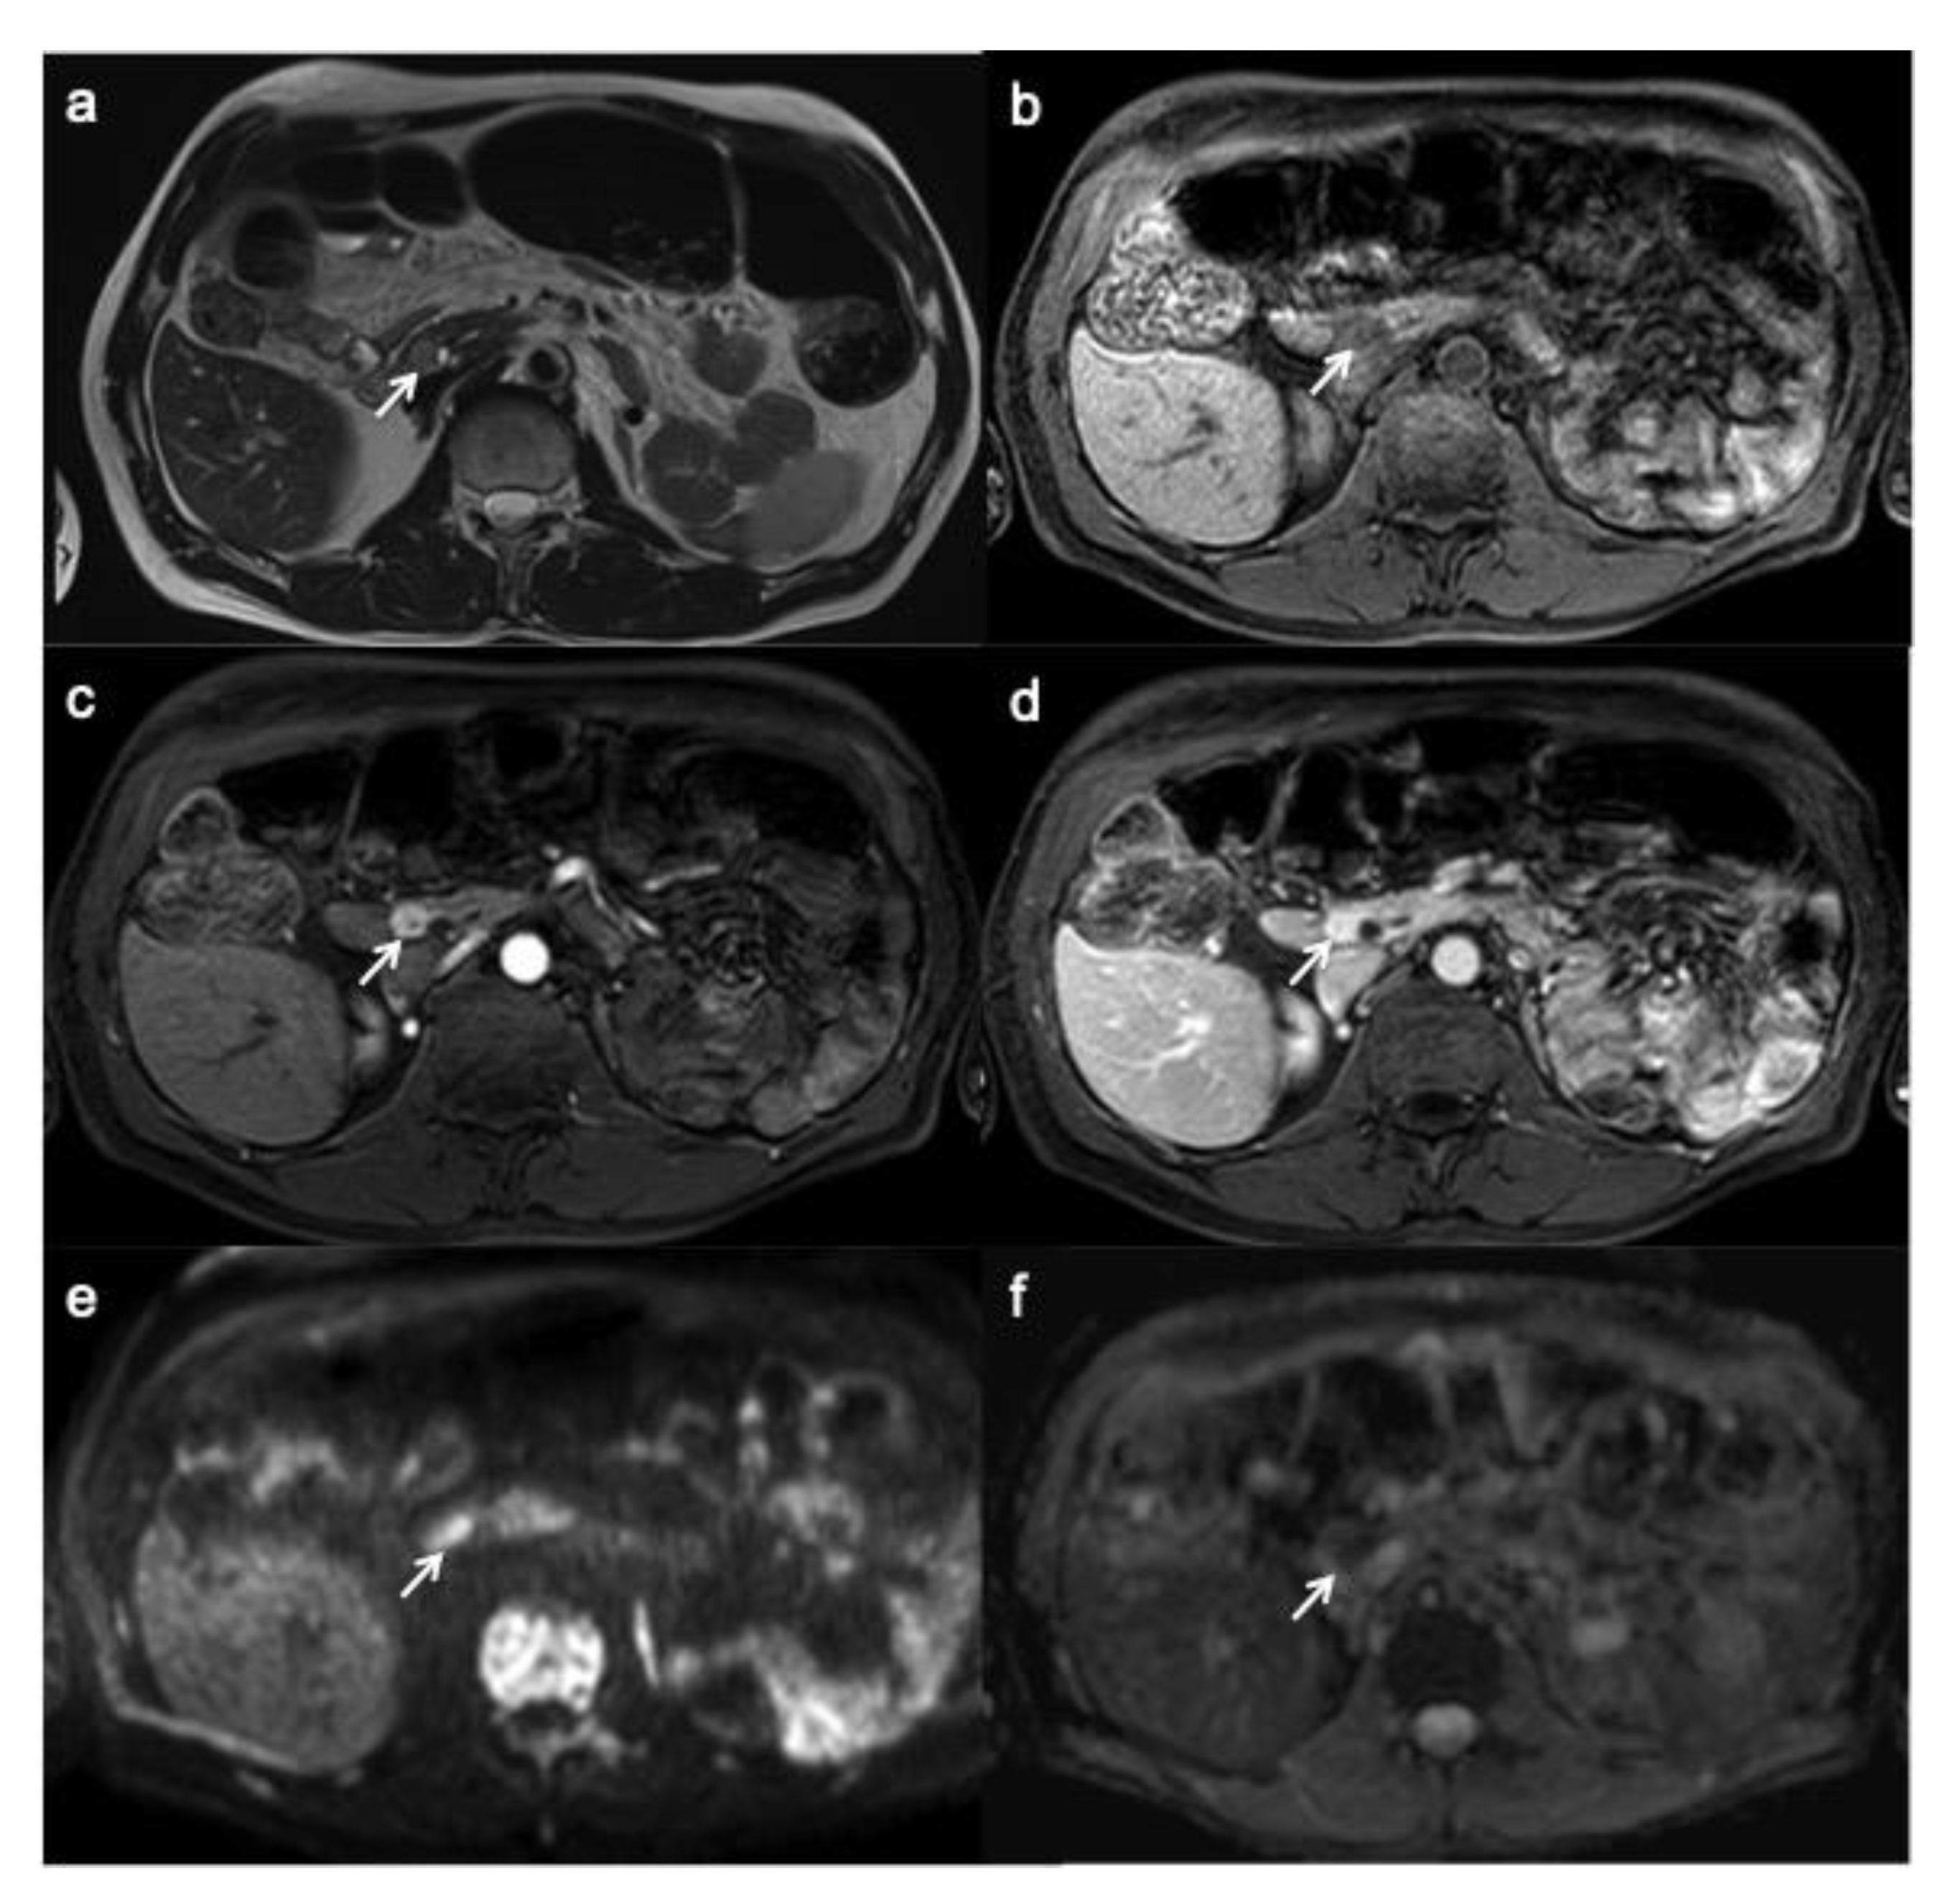

PanNEN appears, on MRI, as a T1 hypo-isointense lesion within the surrounding hyperintense pancreatic parenchyma, T2 hyperintense or less hypointense and, similarly to CT, hyperenhance during arterial phase with a slow washout (Figure 4) [25]; type of enhancement depends on necrotic and hemorrhagic changes.

Figure 4.

Small functioning pancreatic neuroendocrine tumor. T2-weighted MR image (a) shows a small lesion with well-circumscribed margin and high signal intensity (arrow). On T1W image, the lesion appears hypo-intense within the surrounding hyperintense pancreatic parenchyma (b). On contrast enhancement sequences during the arterial (c) and portal (d) phases, the lesion shows hyper-enhancement (arrow). On DWI (e) and ADC map (f), the lesion shows a clearly restrictive pattern.

On MRI, insulinomas show a high signal on T2-weighted imaging, so that they are often better depicted on this sequence, especially with fat suppression than on T1 weighted in the arterial phase [34]. Gastrinomas are hyperintense on T2W images too. However, gastrinomas usually have a ring-enhancement on contrast-enhanced T1weighted imaging, as Semelka et al. found in their study on 22 panNENs. In addition, in their study, they found that the others functioning panNENs usually enhance heterogeneously [43]. Non-functioning panNENs, in contrast to pancreatic adenocarcinoma, show a high signal on T2-weighted imaging and a vivid contrast enhancement during the arterial/pancreatic phase of the dynamic study. The enhancement can be homogeneous or heterogeneous, and ring- or target-like [32].

The use of DWI is increasing in the evaluation of panNENs, which show a clearly restrictive pattern; echo planar diffusion-weighted axial imaging with b-values of 50, 500 and 1000 (with calculated apparent diffusion coefficient (ADC) map) are performed to obtain information about tumor cell density. A lot of studies underlined how DWI is helpful to detect and localize especially small panNENs as insulinomas, thanks to its greater image contrast and functional information [45,46,47]. DWI is particularly useful in those patients with contraindications to contrast medium injection and the association of DWI and T2-weighted images improve detection of panNENs [41,48]. DWI is also useful for metastasis and peritoneal carcinomatosis detection [21,49,50].